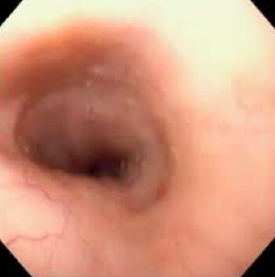

What is the difference b/t these 2 images?